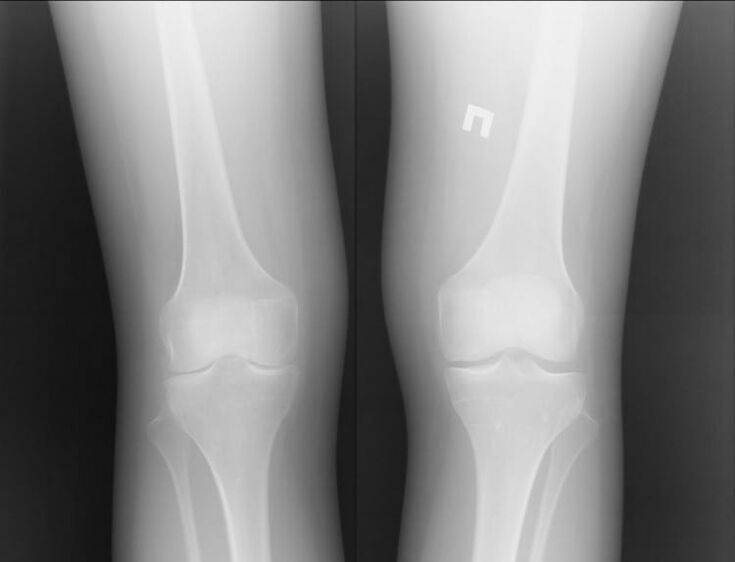

Osteoarthritis is a joint disease caused by cartilage problems.They gradually begin to disintegrate and break down, causing unbearable pain.It occurs in both acute and long-term forms.It often appears in the morning or after intense physical activity.

Joint arthritis is a condition of joint inflammation.Mainly expressed as swelling and redness.The inner lining of the joint is destroyed, causing pain that is often difficult to bear.

Both diseases have a common root in their name "arthron".If you translate it from Greek, you get “joint.”Both diseases are associated with joint problems and pain.Such pathologies occur with acute negative sensations and discomfort.Lesions associated with the cartilage layer limit and complicate movement.

Osteoarthritis and arthritis change the patient's usual lifestyle.It becomes difficult to move, pain appears and the level of resistance decreases - these are the main signs.However, each of these diseases proceeds according to its own scenario.

Osteoarthritis is, in most cases, a chronic disease.For a long time you may not understand that you have this disease, as it manifests itself in the form of temporary aching pain.However, it can proceed quickly or slowly.If arthrosis is not detected in time in the early stages, this disease will lead to disability.Symptoms of osteoarthritis:

Of course, both of these diseases are quite serious and it is difficult to say which is worse.However, we can consider the example of a knee joint problem.With arthritis, that is, with inflammatory processes, the patient can be helped.

Osteoarthritis is a completely different story.This is an independent disease caused by problems in the cartilage tissue.Often this cannot be done without surgery.This is followed by another long recovery process.